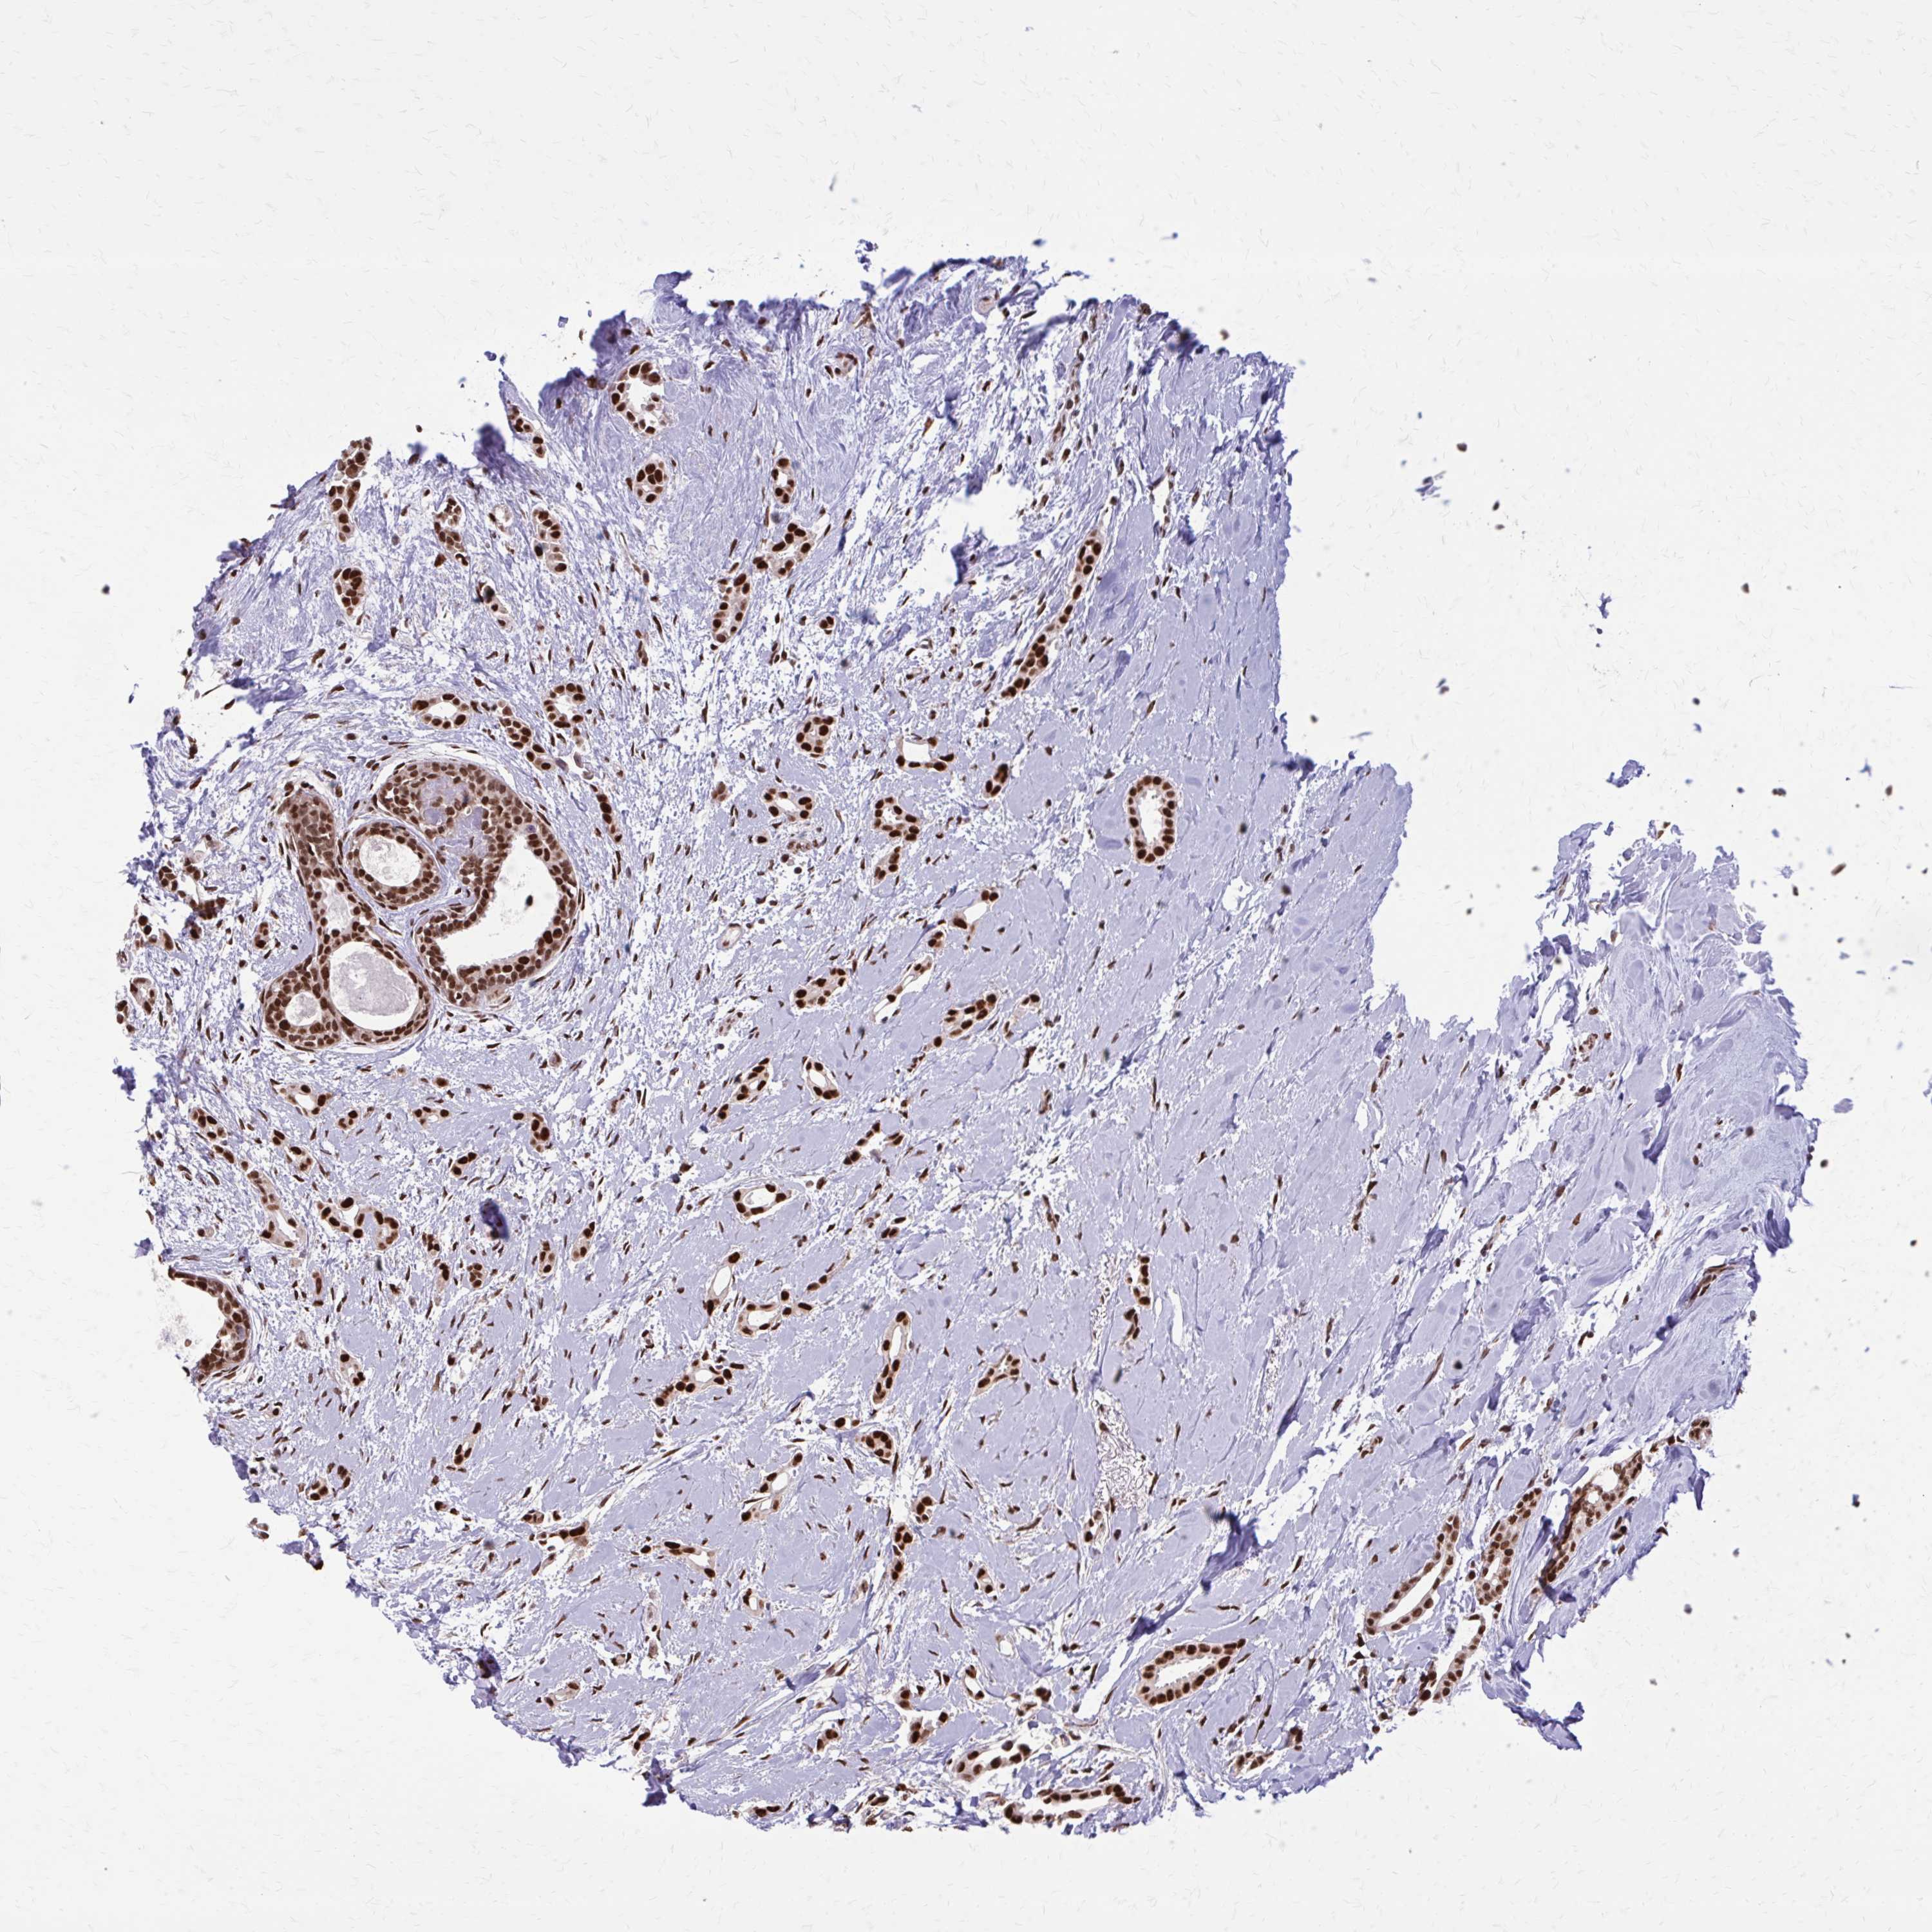

CANCER BREAST CANCER Show tissue menu

BRCA TCGA BRCA VALIDATION PROTEIN EXPRESSION

Breast cancer

Human cancer